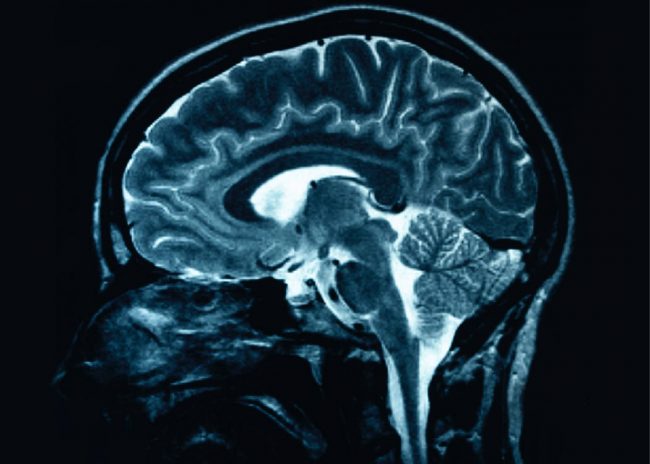

Mercola.com writes about another alternative medicine technique for stroke patients is the curcumin drug. Curcumin, according to the site, is a pigment that gives the tumeric its yellow color, used by the Chinese in the ancient times. The Curcumin compound CNB-001 does not dissolve the blood clots, but repairs the damage due to lack of oxygen and enables the possibility for regeneration of brain cells, according to a study done by Dr. Lapchak, PhD. However, Mercola.com suggests that if someone has signs of stroke, it isn’t wise to reach for the tumeric spice, because it cannot be used as a home remedy. It should be used for patients that have already experienced stroke.